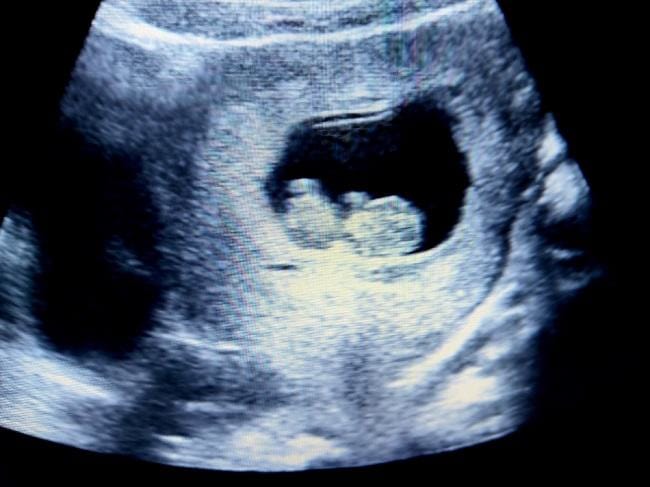

Pada usia janin 10 minggu, ukurannya hanya sebesar buah zaitun atau dengan panjang sekitar 3 cm dan berat 4 gram. Beberapa organ tubuh yang sebelumnya sudah terbentuk makin berkembang, bahkan mulai berfungsi. Si Kecil pun mulai menunjukkan kemiripannya dengan Ayah dan Bunda.

Saat Bunda melihat janin di USG, jangan khawatir bila menemukan ukuran kepala janin 10 minggu kurang lebih setengah dari panjang tubuhnya. Hal ini normal untuk mendukung perkembangan pesat otak janin. Selain ukuran kepala yang terkesan besar, dahi janin pun akan tampak lebih menonjol.

Pada janin 10 minggu, perkembangan pesat otaknya merupakan hal yang paling mengagumkan. Setidaknya terdapat 250 ribu sel saraf terbentuk setiap menitnya pada saat janin menginjak usia 10 minggu. Organ ini juga akan terus berkembang seumur hidupnya.

Bahkan sel-sel pada saraf tulang belakang janin 10 bulan sudah dapat mengirimkan sinyal yang memicu pergerakan kaki dan tangan mungilnya. Namun, karena masih sangat kecil, pergerakan ini akan sulit dilihat melalui USG.